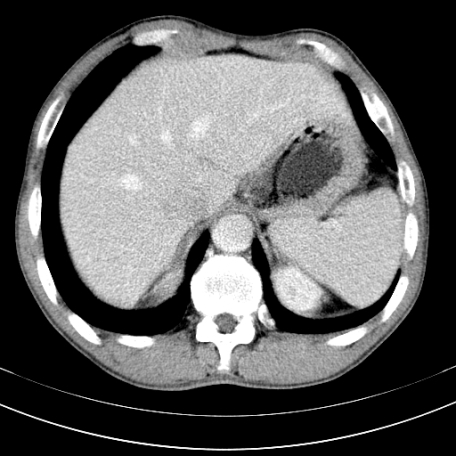

标题: CT21441:男55岁,上腹部胀痛半年余,请老师们看看是后腹膜淋巴 [打印本页]

标题: CT21441:男55岁,上腹部胀痛半年余,请老师们看看是后腹膜淋巴

眼拙!仅见胰腺稍丰满,脾大。

腹膜后淋巴结肿大,原因待查。